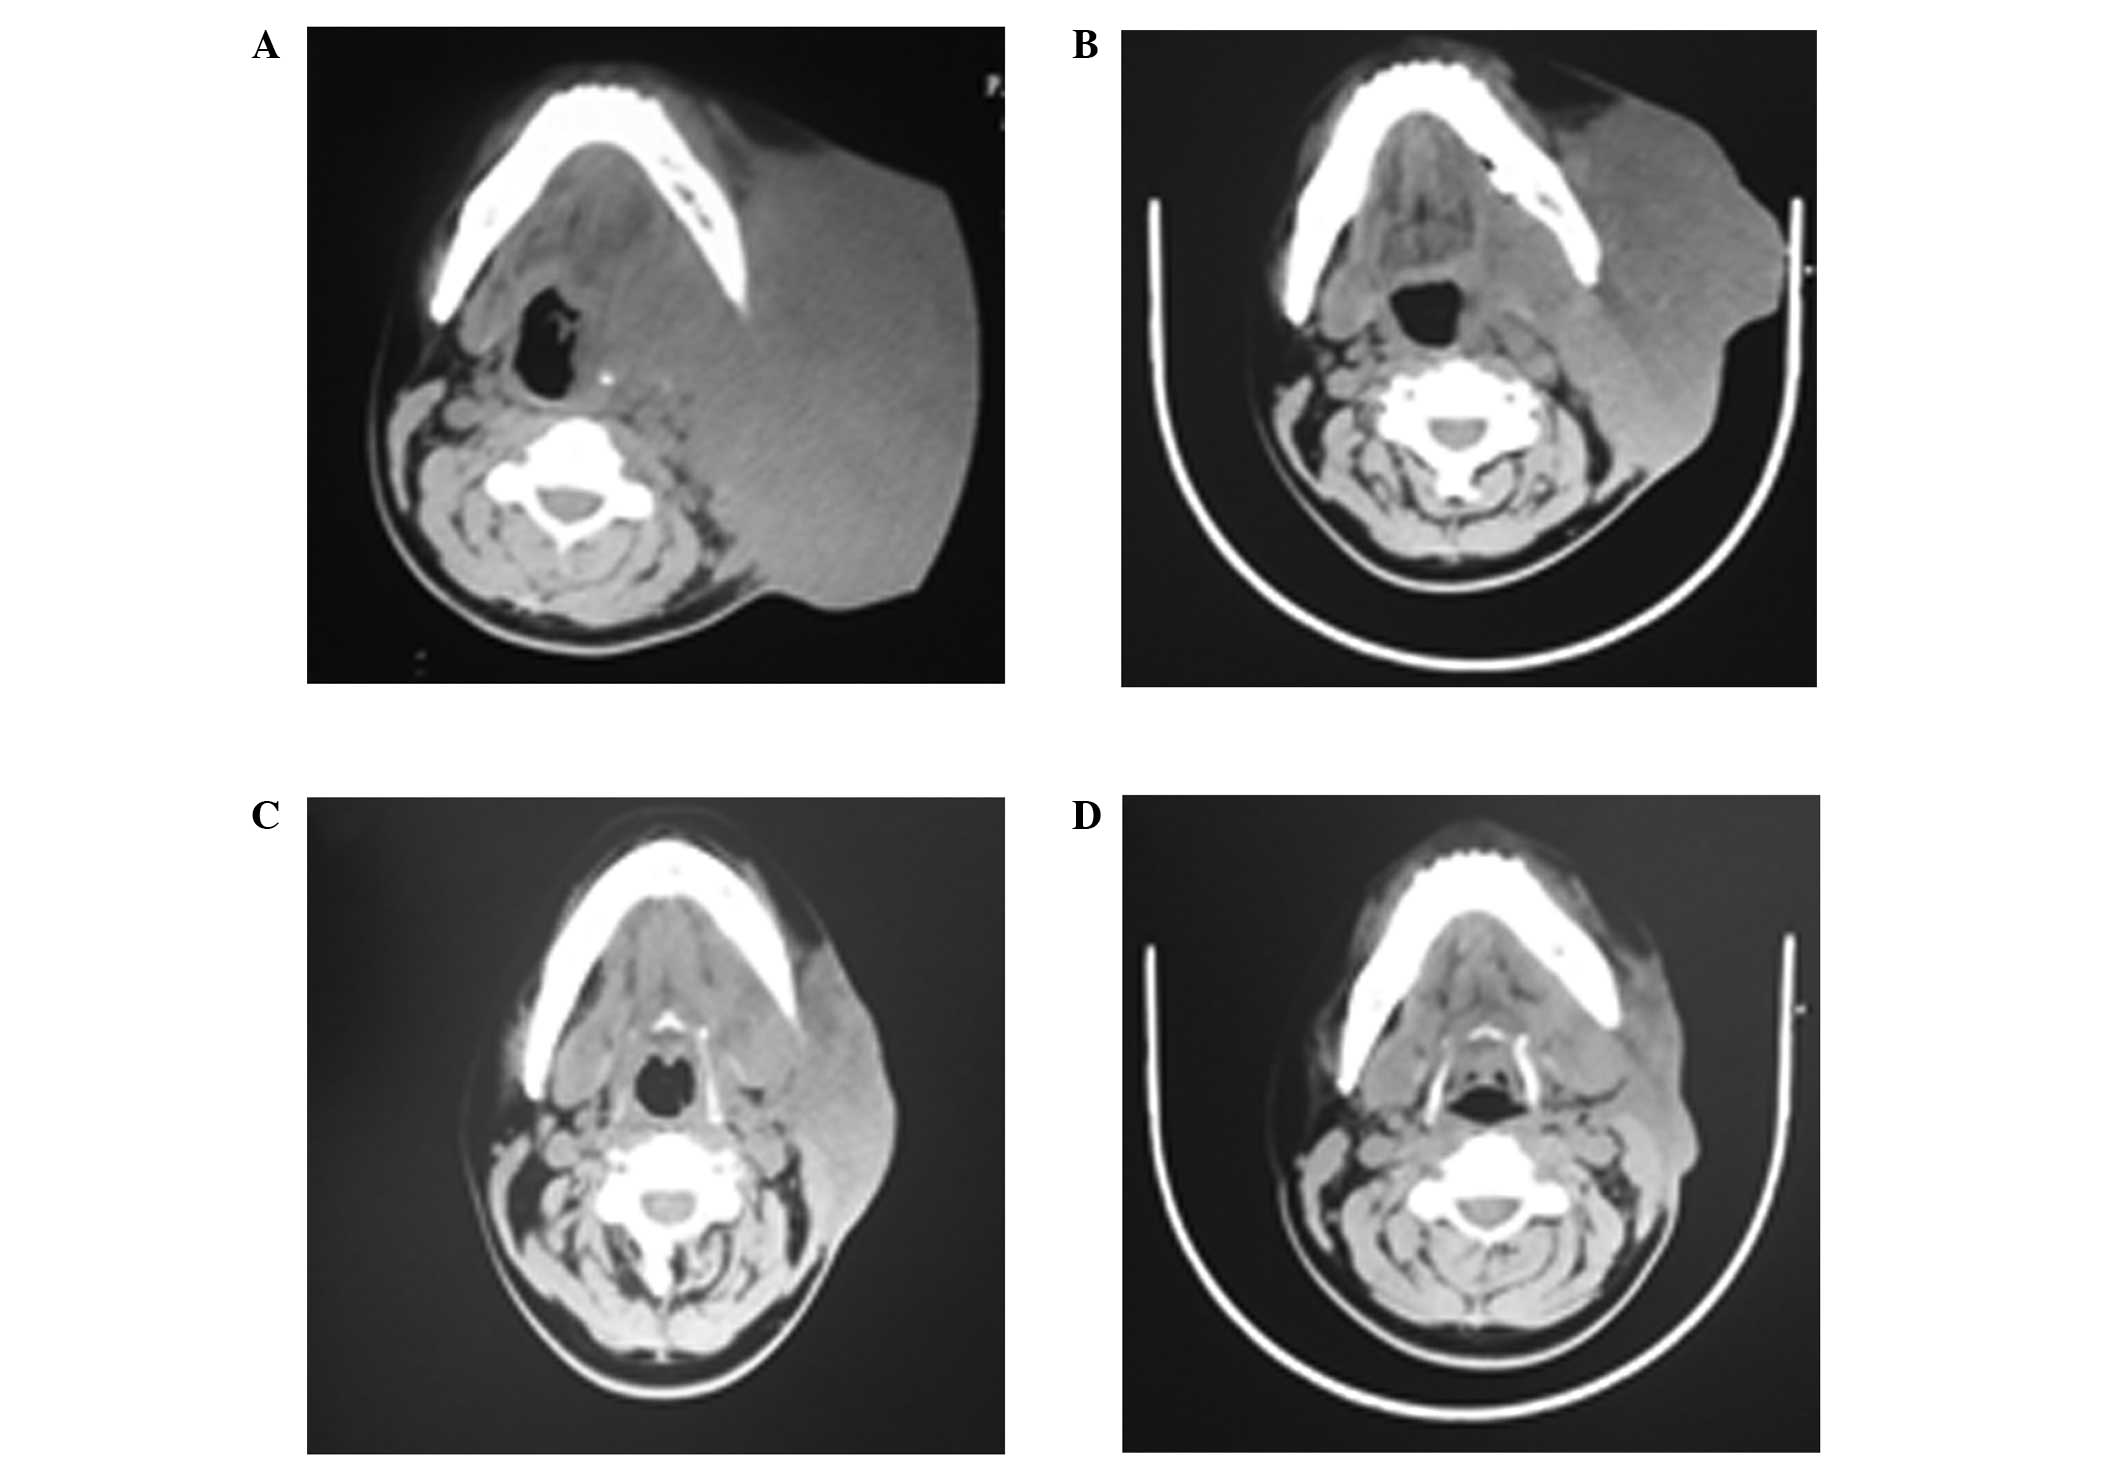

Figure 1

Computerized tomography images of the benign lymphoepithelial lesion in the left parotid gland (A) prior to treatment on May 8 2012, during the treatment on (B) Jun 12 2012 and (C) July 16 2012, and (D) after treatment on Sep 5 2012.

After six months, the left parotid gland became locally swollen again and intermittent management with traditional Chinese medicine was unable to achieve remission. In October 2010, the size of the mass reached 5.0×6.0 cm. A computerized tomography (CT) scan of the parotid gland indicated a soft tissue mass in the left neck area without uniform density or a clear border with the left parotid gland, and evident infiltration in the surrounding tissue. The mass was considered to be a recurrence of the BLEL in the left parotid gland; however, the patient did not agree to further surgical therapy. The mass in the left parotid gland area became gradually enlarged, and was more evident when the patient became ill with a cold; however, the mass was slightly reduced following anti-infective treatment (mainly with cephalosporins). The patient also received traditional Chinese medicine for six months and local acupuncture therapy for 40 days. However, the mass in the left parotid gland area was continually increasing in size and reached a diameter of 15 cm. On April 27 2013, the patient developed a fever of up to 40°C, accompanied with shivering, weakness and a loss of appetite, which was more severe in the afternoon and at night. Remission was observed following self-medication with oral ibuprofen; however, the temperature of the patient increased after several hours and a light yellow, clear liquid was discharged from the ulceration on the skin surface of the left parotid gland mass. On May 4 2013, the patient visited the Jilin Cancer Hospital, where the local ulceration and infection of the left parotid gland mass was managed with anti-infective treatment for three days; however, the high temperature of the patient did not decrease and the mass did not reduce in size. The patient was admitted to the hospital for further therapy on May 8 2013, and physical examination identified a large mass of 17×14 cm on the left side of the patient’s face, a red and swollen skin surface and multiple ruptures in the middle of the mass with a light yellow liquid discharge. The peripheral skin of the mass was tenacious and swollen, and the skin temperature was high. A blood routine examination and liver and renal functions were found to be normal. Color ultrasound revealed a visible 18.2×8.5-cm low-echo area with strong-echo stripes under the skin on the left side of the patient’s face, without the appearance of a clear margin. Color Doppler flow imaging revealed an abundant blood flow in the mass and the absence of normal parotid gland tissue, indicating a solid space-occupying lesion on the left parotid gland. A CT scan of the left parotid gland revealed an abnormal mass in a low-density image and an undefined margin of the lesion, with the superior border extending towards the orbit, the inferior border at the submaxillary level, the inner border at the left parapharyngeal space and the outside border at the skin of the left-side of the face. The mass reached 13.4×9.7 cm in an axial view, showing uniform density and a CT value of 47 HU (Fig. 1A), with the left parotid gland unable to be distinguished. The lesion was wrapped around the left sphenoid bone and mandible. In addition, morphological changes were observed, indicating recurrence of the BLEL in the left parotid gland with bone resorption of the sphenoid bone and mandible. A bacterial culture of the mass discharge indicated a Staphylococcus aureus infection, which was sensitive to levofloxacin. The body temperature of the patient returned to normal levels following the administration of levofloxacin for one week. A biopsy was not performed due to the weakness, high fever, local swelling and infection of the patient, as well as the abundant blood flow detected in the mass with color ultrasound. No consensus was reached with regard to further surgical intervention. Drugs inhibiting vascular endothelial growth (Endostar and Shenyi capsules) were administered for five days, but were discontinued by the patient due to local pain and swelling. Chemoradiotherapy was subsequently considered; however, due to the young age of the patient and the examination results not indicating malignance, the patient did not agree to the therapy.

Parotid gland CT scans (Fig. 1B–D) indicated that the primary lesion of the left parotid gland area disappeared gradually and the bone destruction was completely recovered. The patient was discharged from hospital and the condition remained stable without signs of recurrence during a follow-up period of 10 months; however, the patient remains under close observation.